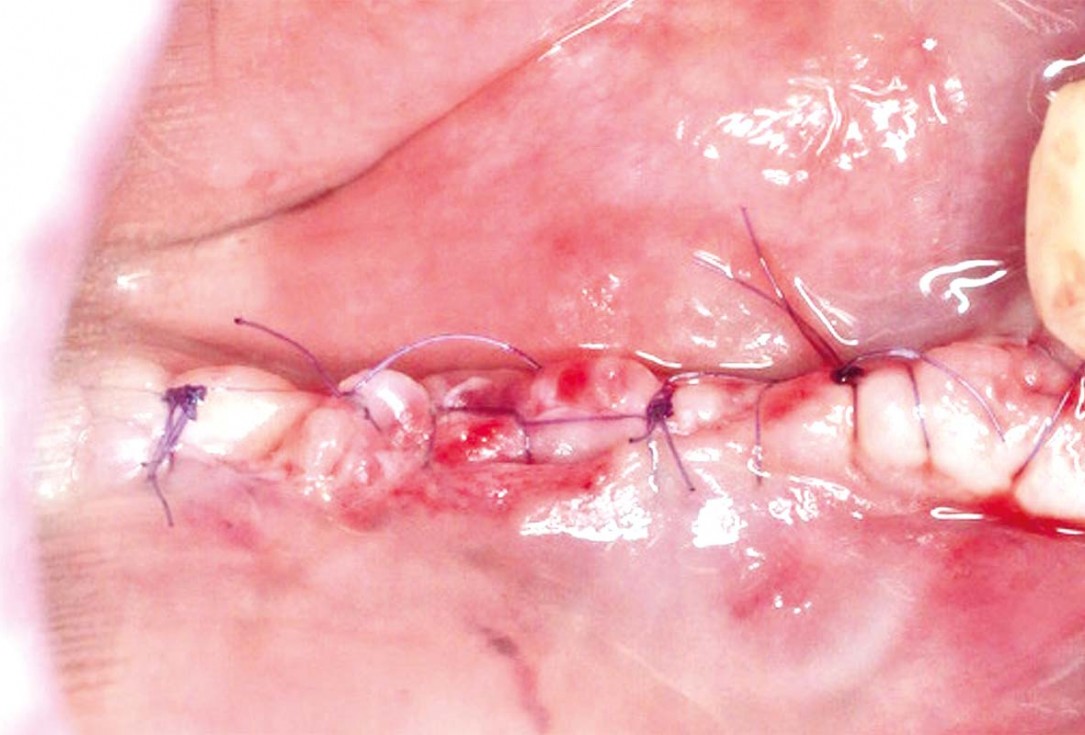

07/10 - Situation 12 months post-operative, before membrane removal.

Vertical and horizontal GBR using permamem®, cerabone® and autologous bone - Dr. D. B. Hangyasi